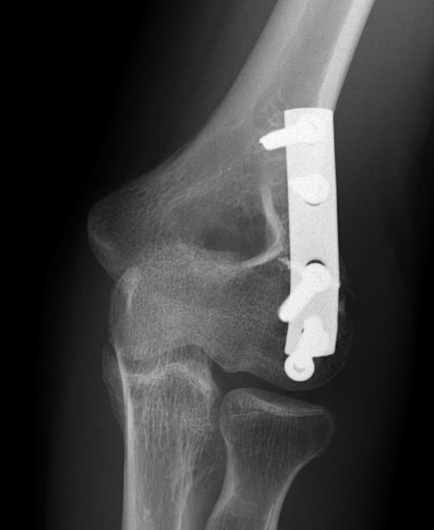

Lateral approach and ORIF

ORIF with AP screws

ORIF Type II with screws